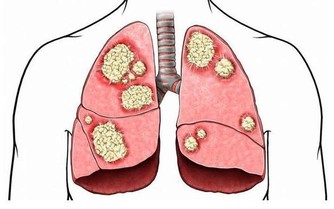

靈芝含有抗癌效力的多醣體,還含有豐富的鍺元素,能加速身體的新陳代謝,延緩細胞的衰老,增強人體的免疫力。可以用靈芝煮粥,將靈芝切成1~3毫米薄片。

用水煎後,取汁與大米同煮,或待粥熟後調入靈芝粉5g服食。MH推薦靈芝孢子粉,每天1~2勺,再配合其他食品增強免疫力的效果更佳。靈芝孢子粉已經成為健康專家公認的提升免疫力的補品。